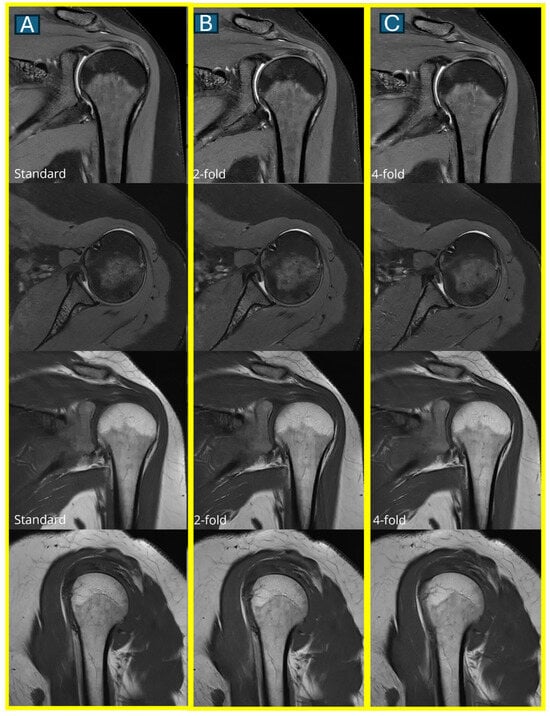

Figure 4. A comparison of image quality across all three protocols. Representative axial and coronal MRI images show a normal rotator cuff in a 45-year-old male. Images in the first column show the standard protocol (A), the second column shows the DL2 protocol (2-fold acceleration) (B), and the third column shows the DL4 protocol (4-fold acceleration) (C). Note the progressive subtle loss of fine detail with increasing acceleration, though all protocols maintain diagnostic quality.